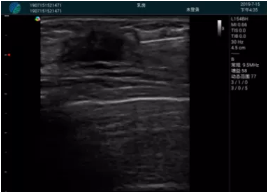

甲狀腺囊性結節(jié),囊壁鈣化,透聲好

甲狀腺囊性占位